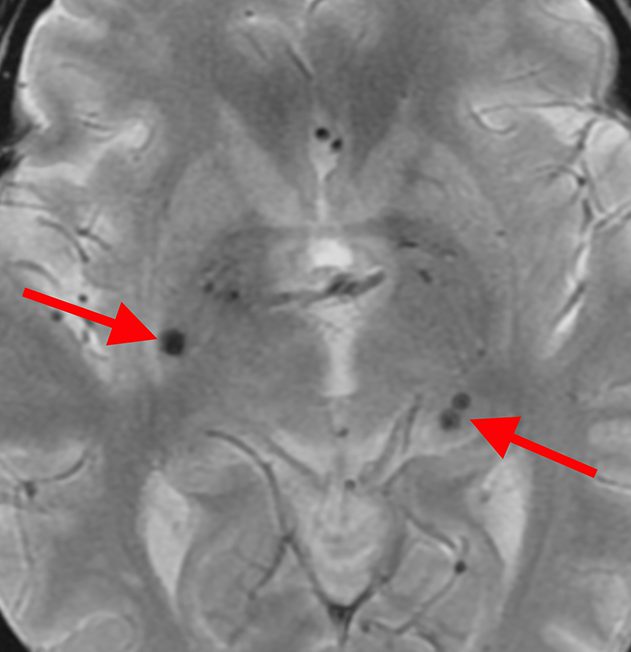

微小脳梗塞

高血圧や糖尿病が原因で脳の細い動脈が詰まって生じます。

微小脳出血

高血圧が原因で脳の細い動脈が破綻して生じます。